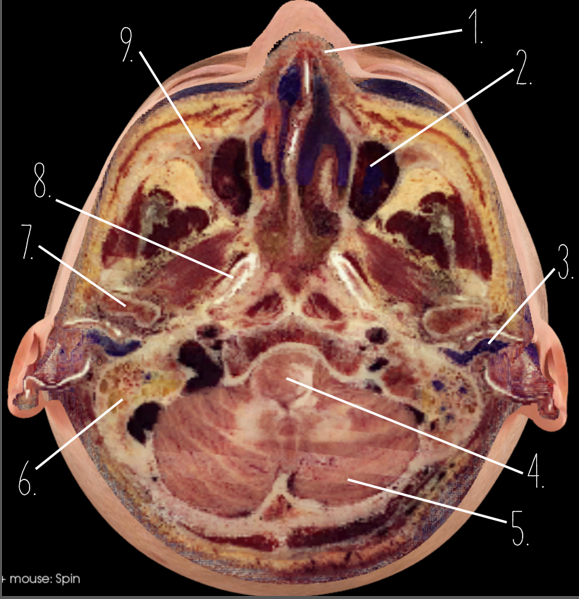

1?

Nasal Bone

2?

Maxillary Sinus

3?

External Acoustic Meatus

4?

Pons

5?

Cerebellum

6?

Mastoid Air Cells

7?

Mandibular Condyles

8?

Sphenoid Bone

9?

Maxillary Bone